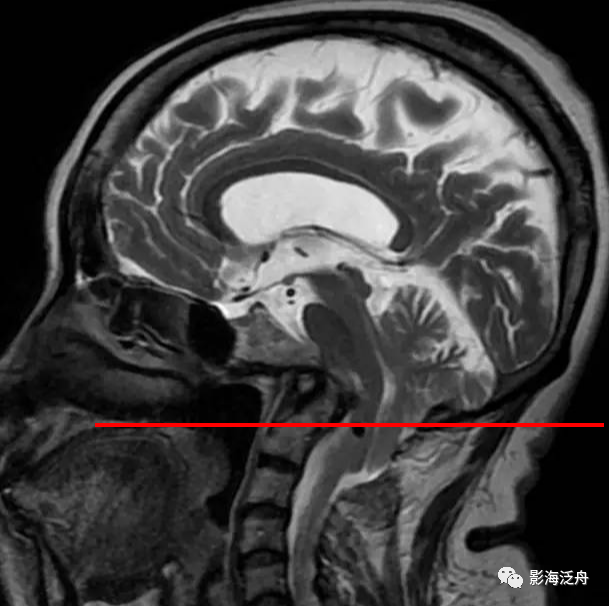

矢状位上另一个需要观察的就是齿状突的高度,异常增高往往是颅底凹陷症导致的(红线为钱氏线)。